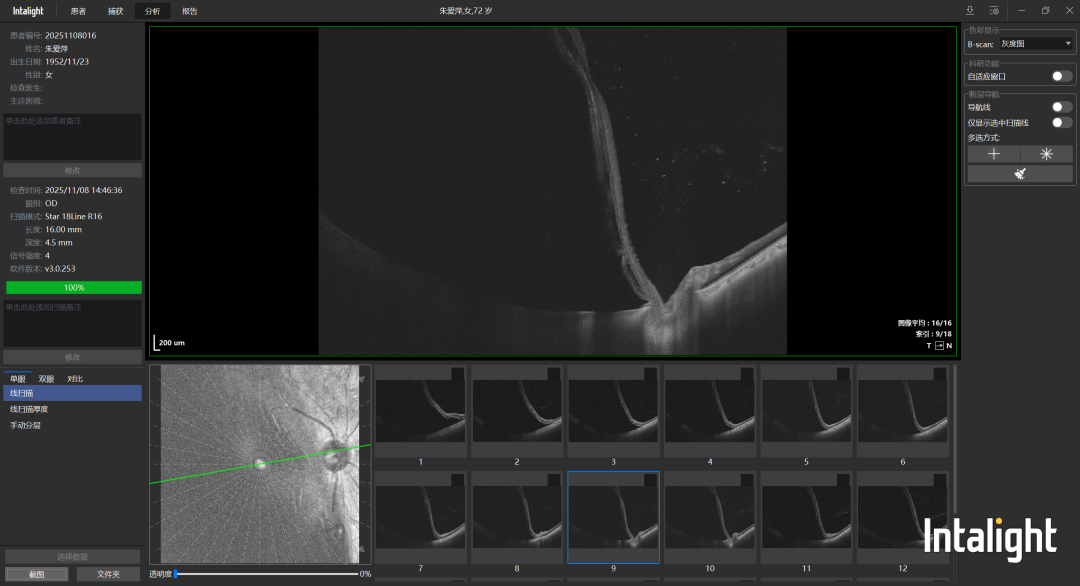

(视网膜震荡)